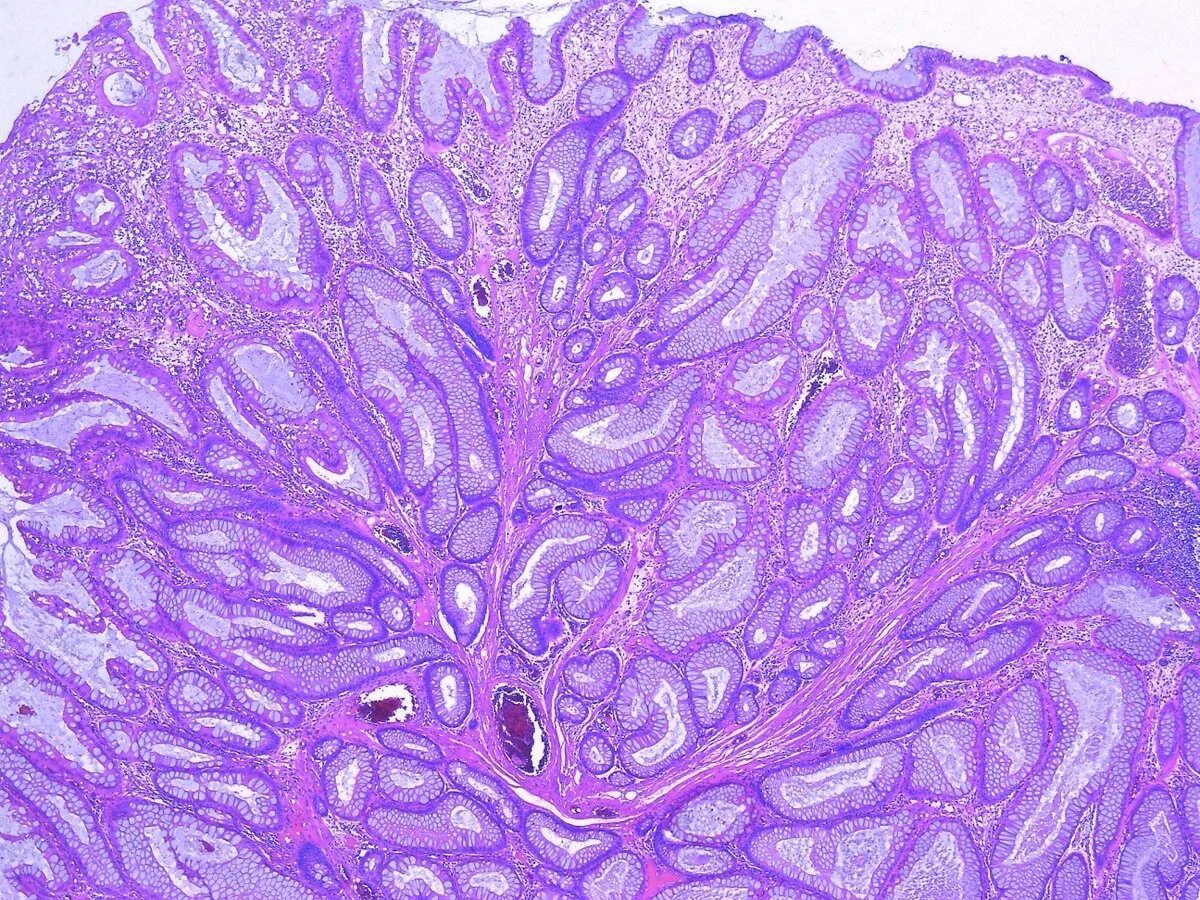

Гистологический срез это